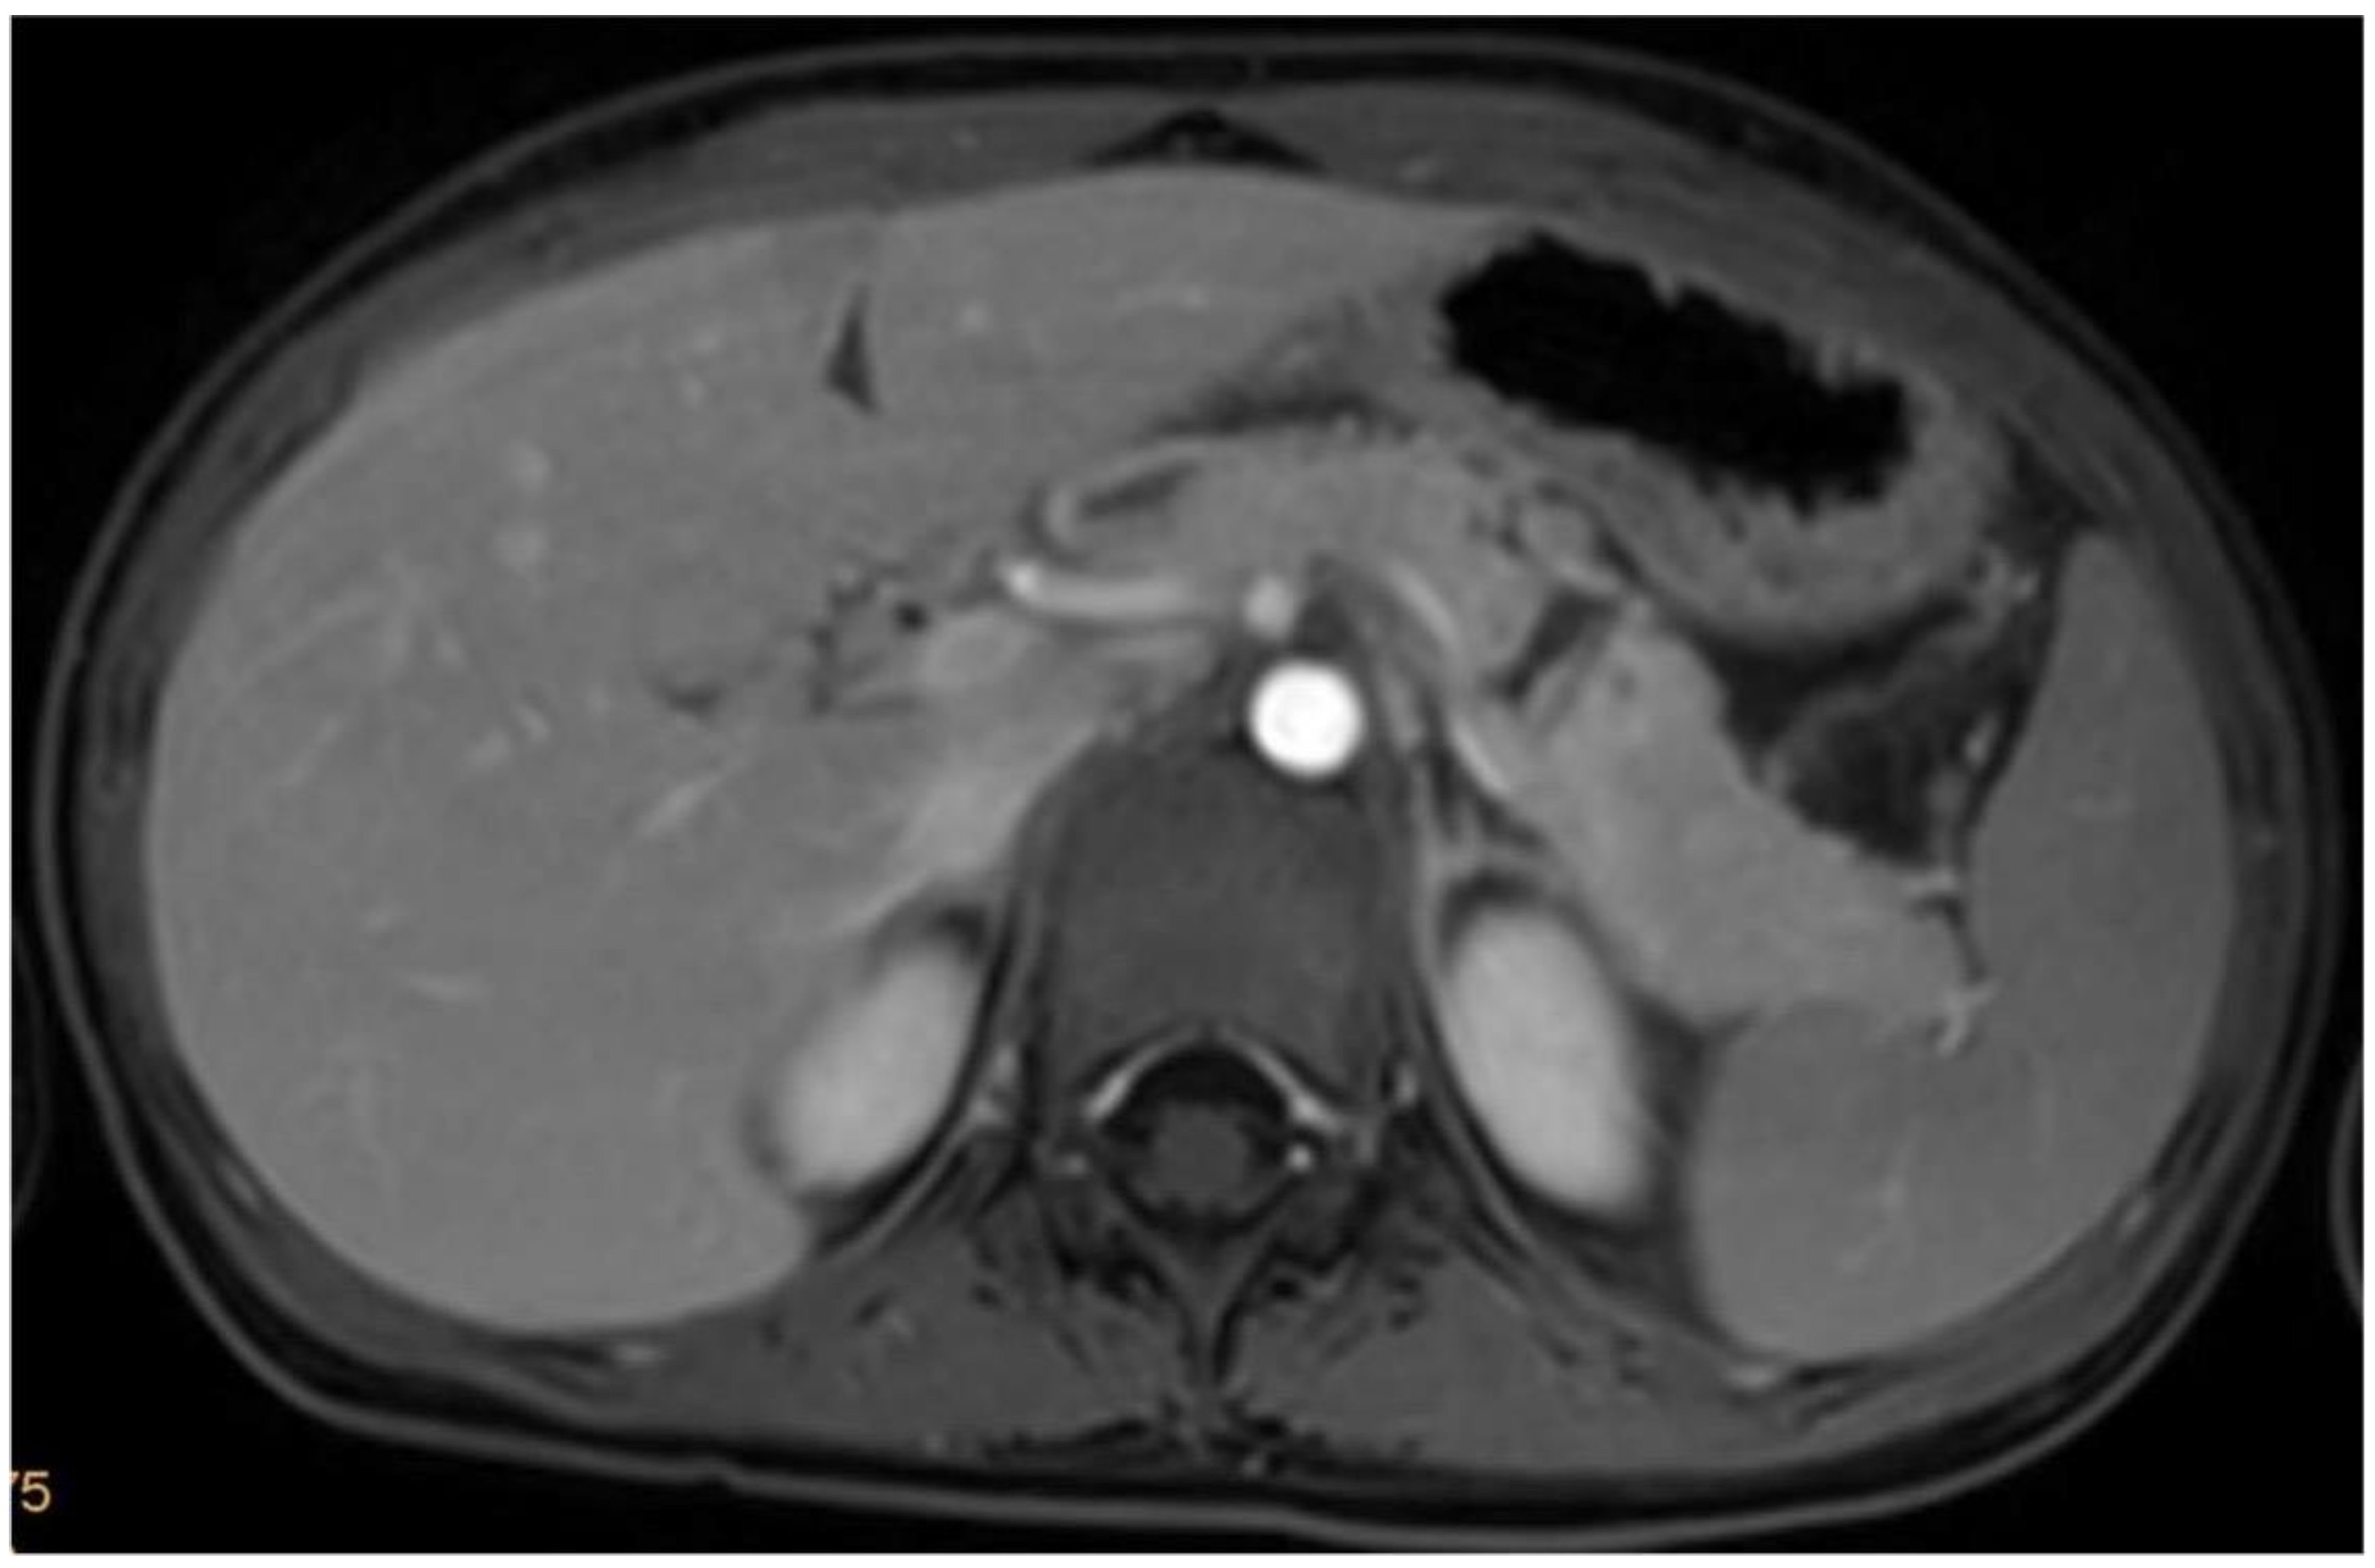

| Initial diagnosis obtained by | Computed Tomography | Computed Tomography | Magnetic Resonance Tomography | Computed Tomography |

| Grade of Pancreatic Injury | IV | IV | III | III |